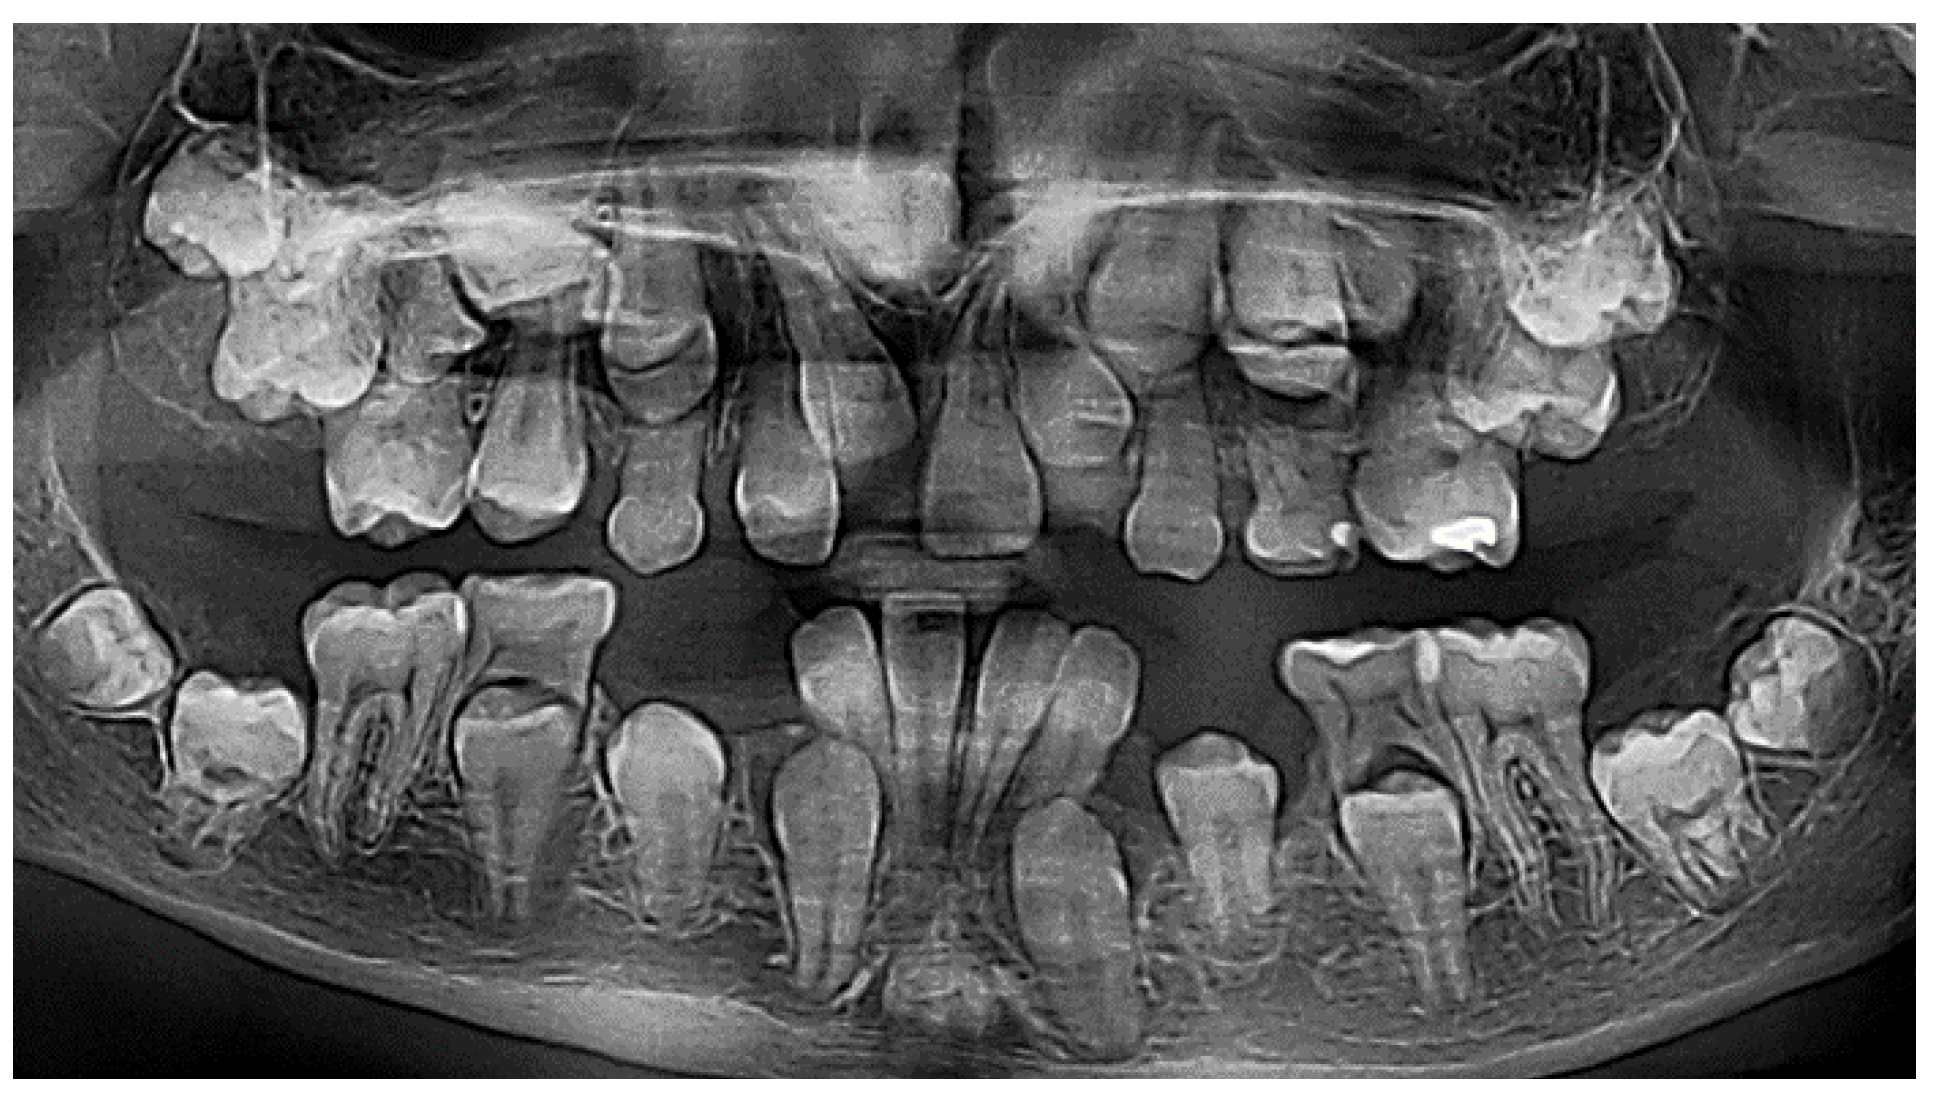

On the panoramic radiographic image (OPG) taken in April 2013 (Figure 1.) there was a finding of over-retained deciduous teeth with unresorped roots. The dental age was estimated according to the Demirjan method, 4,6 years in the upper dental arch and 6,9 in the lower. Three supernumerary teeth were present in the upper jaw, and two in the lower, displacing the developing permanent teeth and obstructing their eruption. All regular permanent teeth buds were in place, some of them were retarded in eruption also because of a lessened eruptive potential. There was a serious (approximately 3 years) delay in the root development of the permanent teeth. The dental age was estimated according to the developmental stages of the roots of permanent teeth and resorption stages of deciduous predecessors – the Demirjan method [19,22].

The three-dimensional (3D) reconstruction of the CBCT x-ray, taken in May 2013 revealed three more supernumerary empty tooth crypts in the upper jaw and proved the two supernumerary teeth in the lower. The patient had had 8 supernumerary teeth at that time. (Figure 1.,6.,7.)

Two surgical interventions in general anesthesia were planned in the upper jaw, provided that no more supernumerary teeth develop from empty, non-mineralized supernumerary dental crypts, which are usually difficult to localize on early CBCT scans. One surgical intervention under general anesthesia was planned in the lower arch to extract the two supernumerary teeth in the premolar area. (Figure 1)

Figure 1. The initial OPG x-ray of the patient (2013).